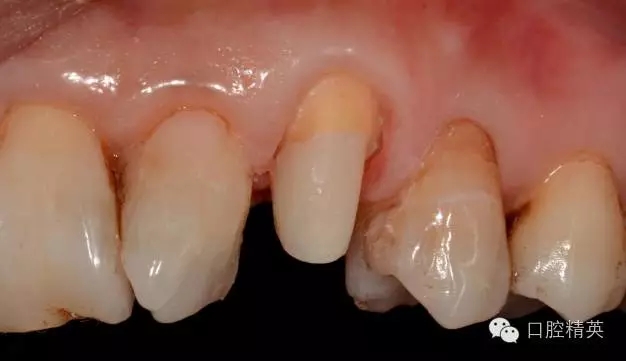

圖5 置纖維樁樹脂樁備牙后情況